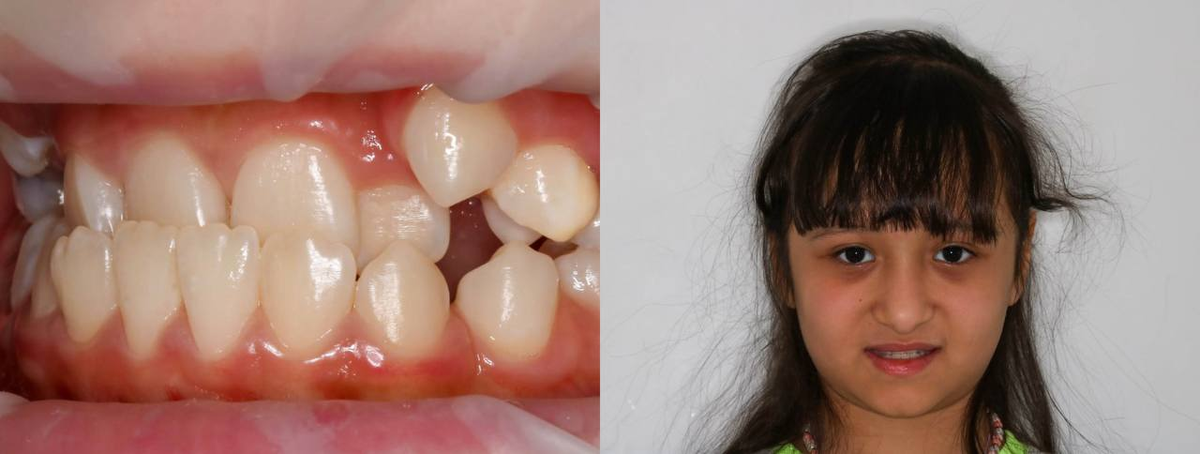

Запрос родителей звучал просто и очень тревожно: «Ребёнок больше не улыбается. Стесняется. Над ней смеются в школе». К этому добавлялись: — трудности с жеванием, — проблемы с откусыванием пищи, — нарушение носового дыхания. Осмотр и диагностика За внешне «просто неровной улыбкой» скрывалась серьёзная функциональная проблема: — нижняя челюсть полностью перекрывала верхнюю, — выраженное смещение челюсти вбок, — формирующаяся асимметрия лица, — перегрузка мышц и сустава. Мы начали с полной диагностики и санации. Сохранили 8-е зубы, что при 3 классе прикуса удаётся далеко не всегда и требует функционального мышления, а не шаблонных решений. После большого функционального анализа (аксиография, анализ моделей в артикуляторе, виртуальный сетап и др) было проведено планирование этапов лечения пациента. ВАЖНО: лучший момент для коррекции прикуса у детей — до 7 лет. Диагностика показала 🔸 полный перекрёстный прикус во фронтальном и жевательных отделах 🔸 критически сниженную высоту нижней трет

За внешне «просто неровной улыбкой» скрывалась серьёзная функциональная проблема:

— нижняя челюсть полностью перекрывала верхнюю,

— выраженное смещение челюсти вбок,

— формирующаяся асимметрия лица,

— перегрузка мышц

и сустава.

Диагностика показала

🔸 полный перекрёстный прикус во фронтальном

и жевательных отделах

🔸 критически сниженную высоту нижней трети лица

🔸 недоразвитие верхней челюсти

🔸 доминирование нижней челюсти

🔸 суженные зубные ряды

🔸 латеральное смещение нижней челюсти